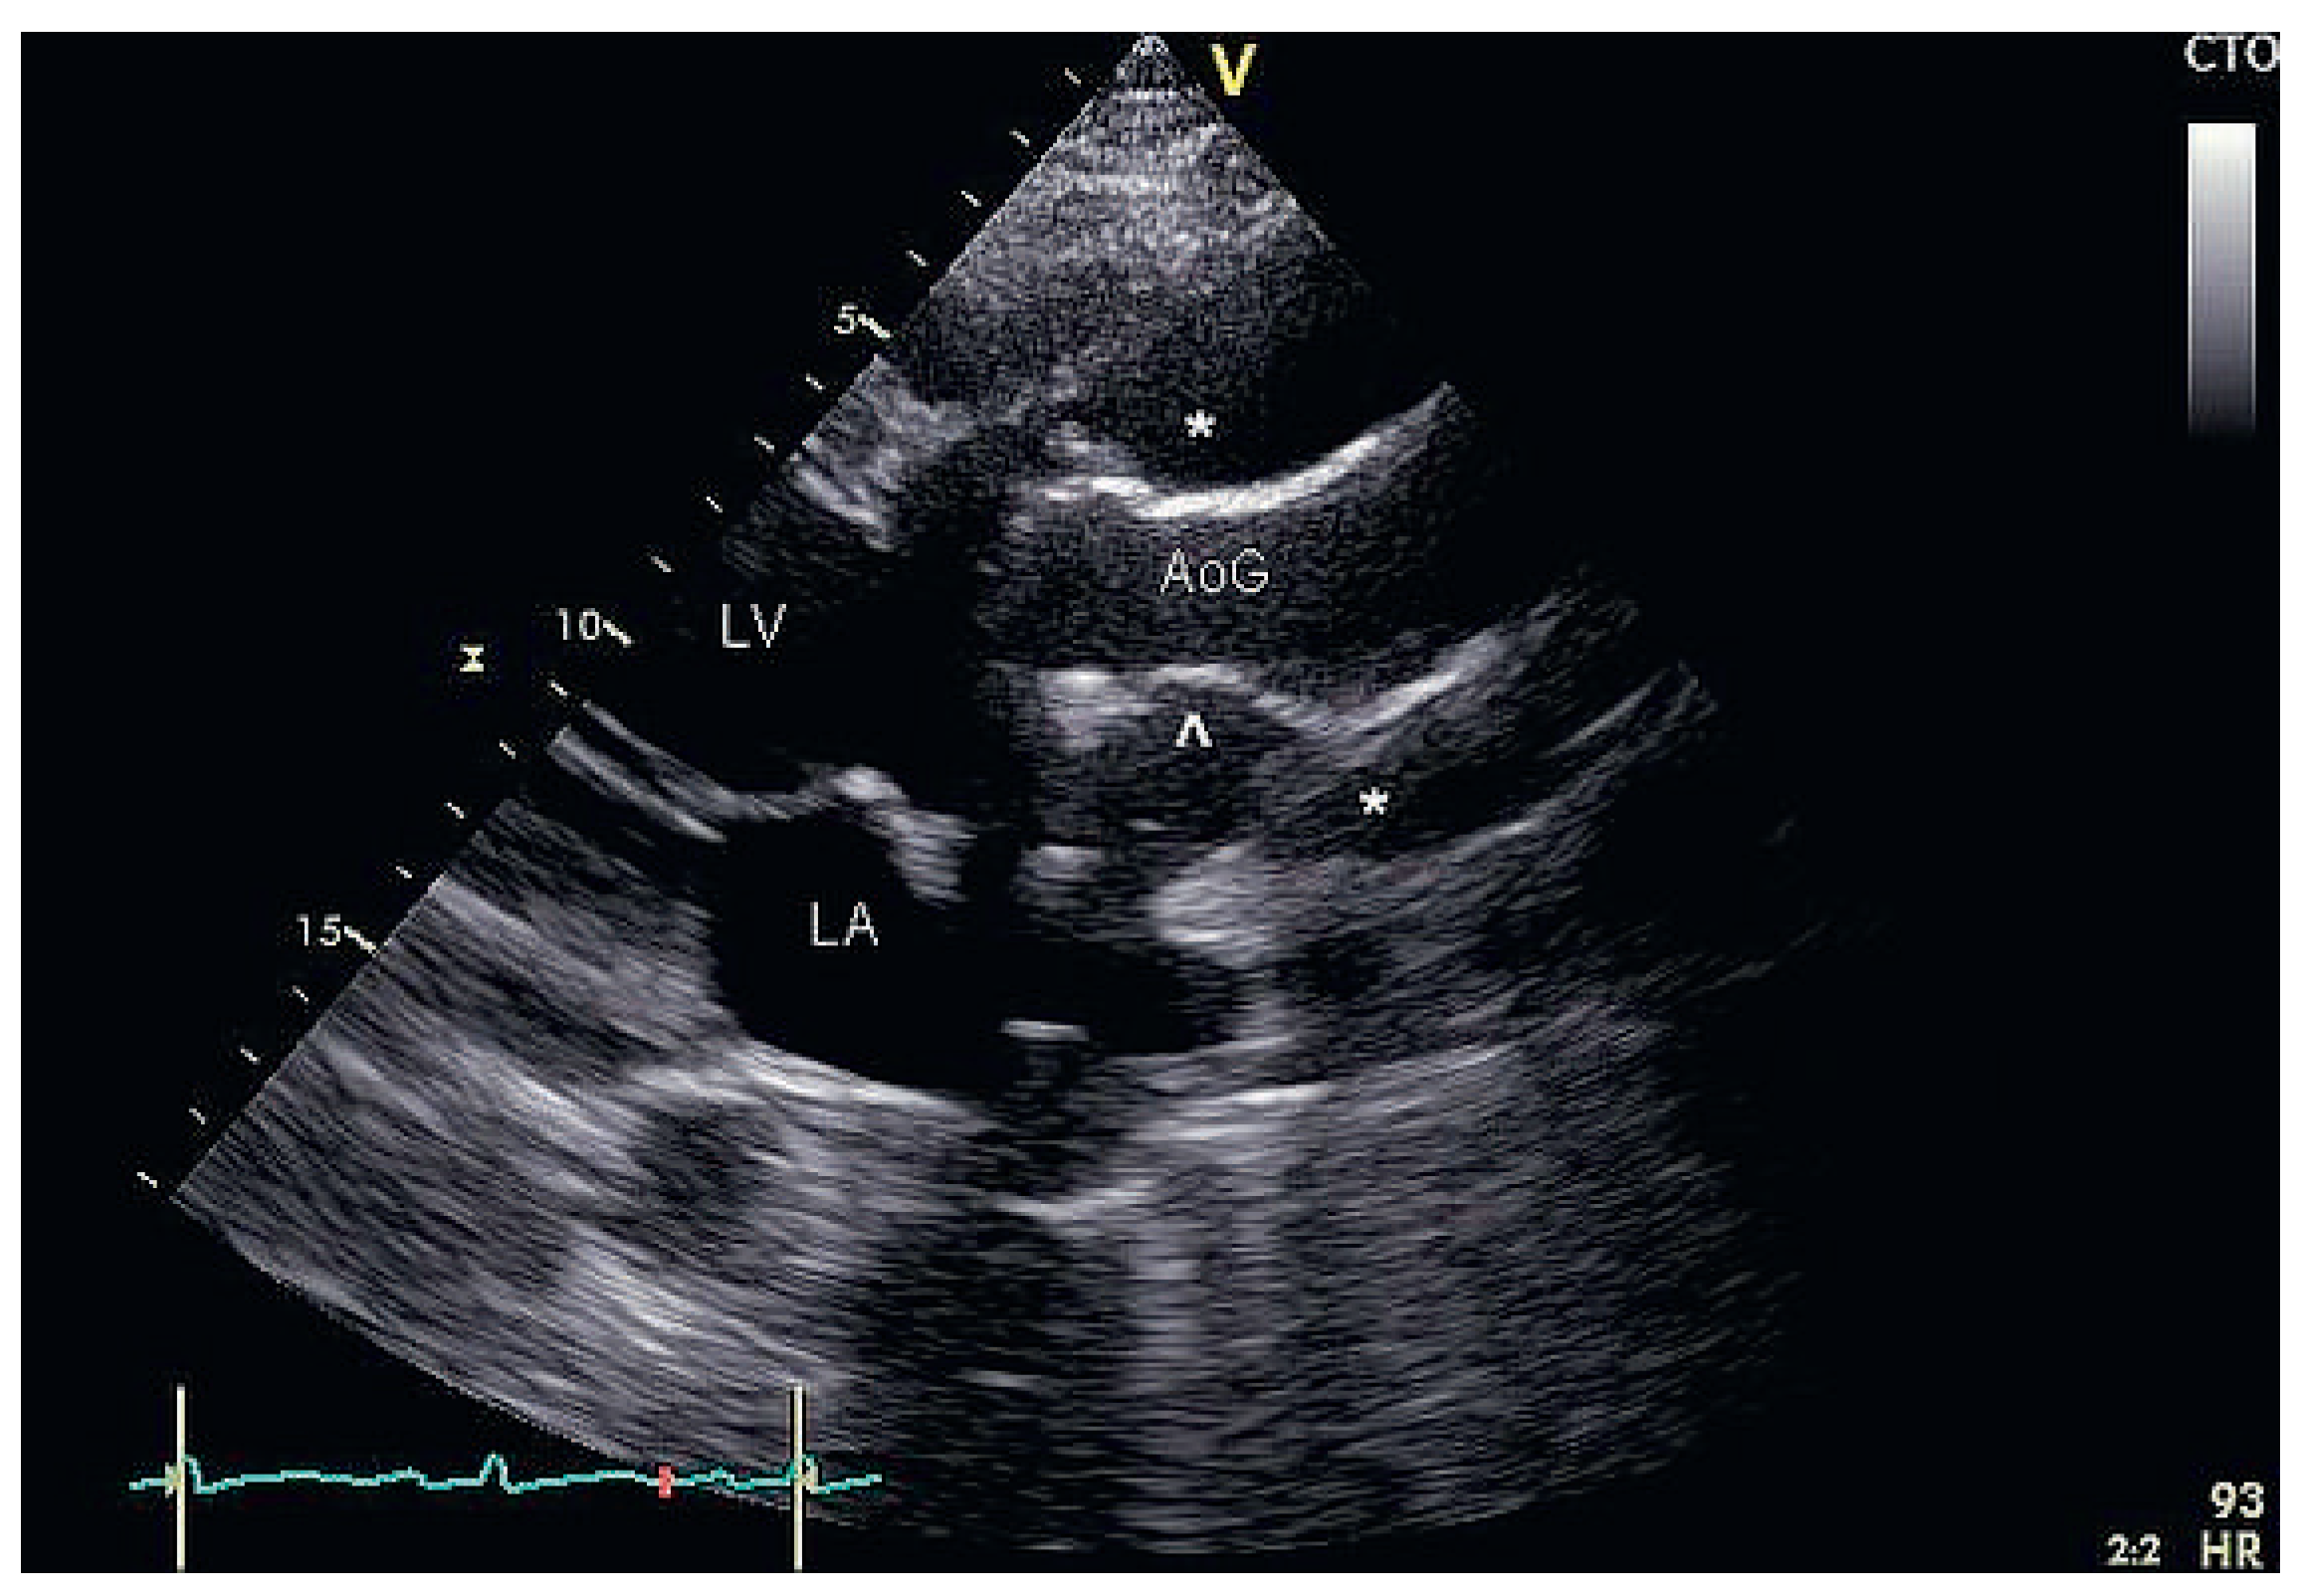

Partial Aortic Graft Disconnection Due to Endocarditis: A Rare Cause of Dynamic Coronary Artery Compression